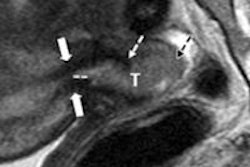

They also noted that accuracy levels in detecting cancer invasion of the myometrium, cervical stroma, parametria and/or adnexae, and vagina, respectively, were 72%, 69%, 74%, and 85% for reader 1 and 78%, 77%, 76%, and 85% for reader 2.